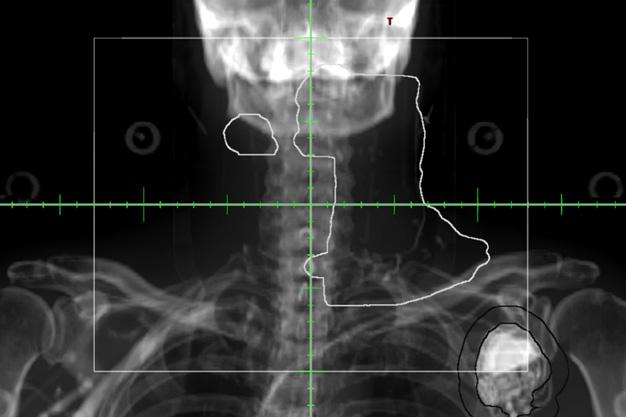

4. Évaluation de la vascularite des gros vaisseaux : il s’agit d’un groupe de troubles caractérisés par une inflammation des vaisseaux sanguins, affectant principalement les grosses artères (figure 2). Ces affections peuvent provoquer des symptômes comme la fièvre, la fatigue et des douleurs ou une raideur dans les épaules, les hanches et le cou. La TEP-FDG peut être utilisée pour visualiser l’activité métabolique des vaisseaux sanguins et détecter les

Figure 1 : Exemple de TEP-FDG chez une personne atteinte de sarcoïdose cardiaque. Outre la détection de l’inflammation du myocarde, la TEP-FDG du corps entier permet de détecter les emplacements atteints à l’extérieur du cœur et d’obtenir davantage d’information sur le stade de la maladie.

Figure 2 : La TEP-FDG est un examen précis et simple pour l’évaluation de la vascularite. Chez cette personne atteinte d’une vascularite des gros vaisseaux, on observe un niveau élevé d’absorption dans la région de l’aorte abdominale.

zones d’activité accrue pouvant indiquer une inflammation. En comparant le niveau d’absorption du FDG dans les vaisseaux sanguins à celui d’un tissu sain normal, les médecins peuvent identifier les zones d’inflammation et évaluer l’étendue des dommages subis par les vaisseaux sanguins. La TEP-FDG peut également être utilisée pour surveiller l’évolution de la vascularite des gros vaisseaux ainsi que l’efficacité du traitement. L’examen peut aider à identifier une rechute précoce de la maladie et à évaluer la nécessité de modifier les plans de traitement. Dans l’ensemble, la TEP-FDG est un outil utile pour le diagnostic et la prise en charge de la vascularite des gros vaisseaux, car elle peut fournir des informations précieuses sur l’étendue et la gravité de l’inflammation dans les vaisseaux sanguins, ainsi que guider les décisions relatives au traitement et en surveiller l’efficacité.